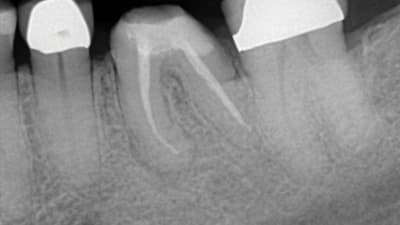

Continuing Education CE Articles Digital Imaging CBCT in the General Practice By Jon Julian, DDS July 01, 2021